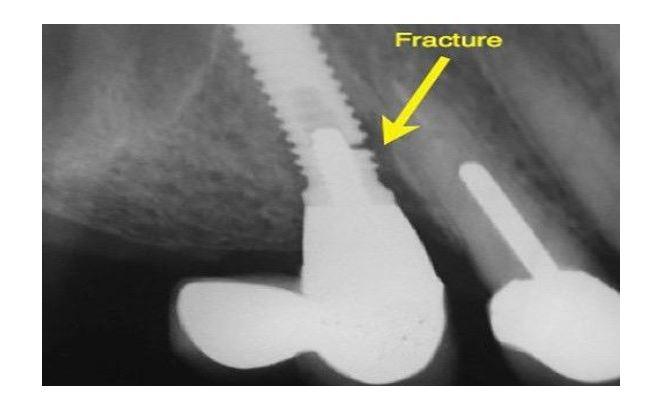

Một trường hợp vỡ cổ implant do điều trị không tốt và vật liệu không đạt tiêu chuẩn.

Điều đáng lo ngại là những biến chứng này thường chỉ được phát hiện khi đã ở giai đoạn muộn, khiến việc xử lý trở nên phức tạp và tốn kém hơn rất nhiều.